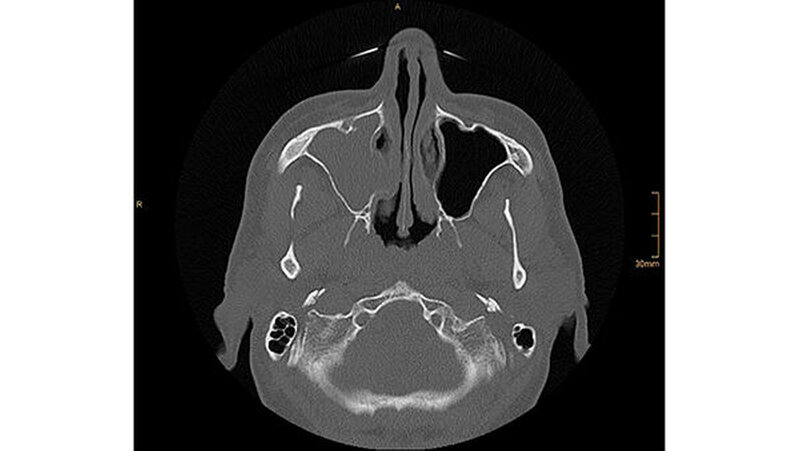

Die CT-Aufnahmen zeigen eine deutliche bis zum Orbitaboden heranreichende Totalverschattung der rechten Kieferhöhle. In Höhe des Zahns 16 zeigen sich periradikuläre Rarefikationen als Hinweis auf eine aggressive lokale Parodontitis.